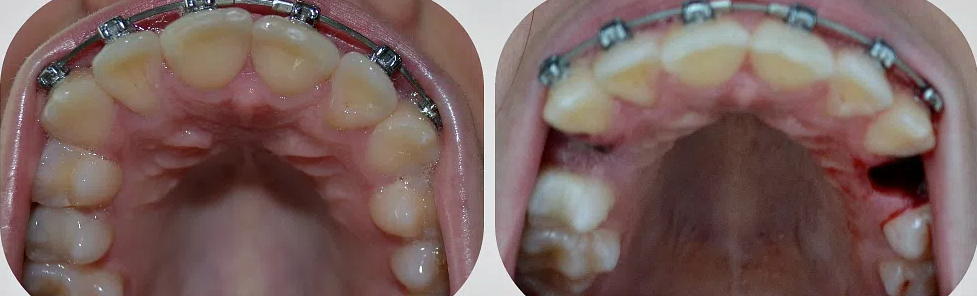

Удаление корня зуба: фото до и после